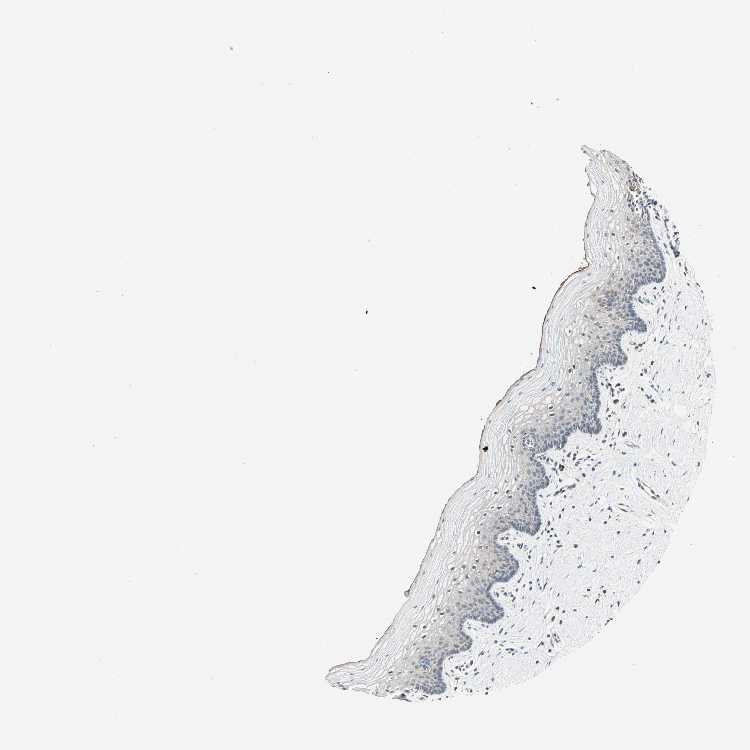

VAGINA - Antibody stainingi

Antibody staining in the annotated cell types in the current human tissue is reported as not detected, low, medium, or high, based on conventional immunohistochemistry profiling in selected tissues. This score is based on the combination of the staining intensity and fraction of stained cells.

Each image is clickable and will lead to virtual microscopy that enables deeper exploration of all samples and also displays staining intensity scores, fraction scores and subcellular localization as well as patient and tissue information for each sample.

Antibody HPA007636

Squamous epithelial cells Not detected